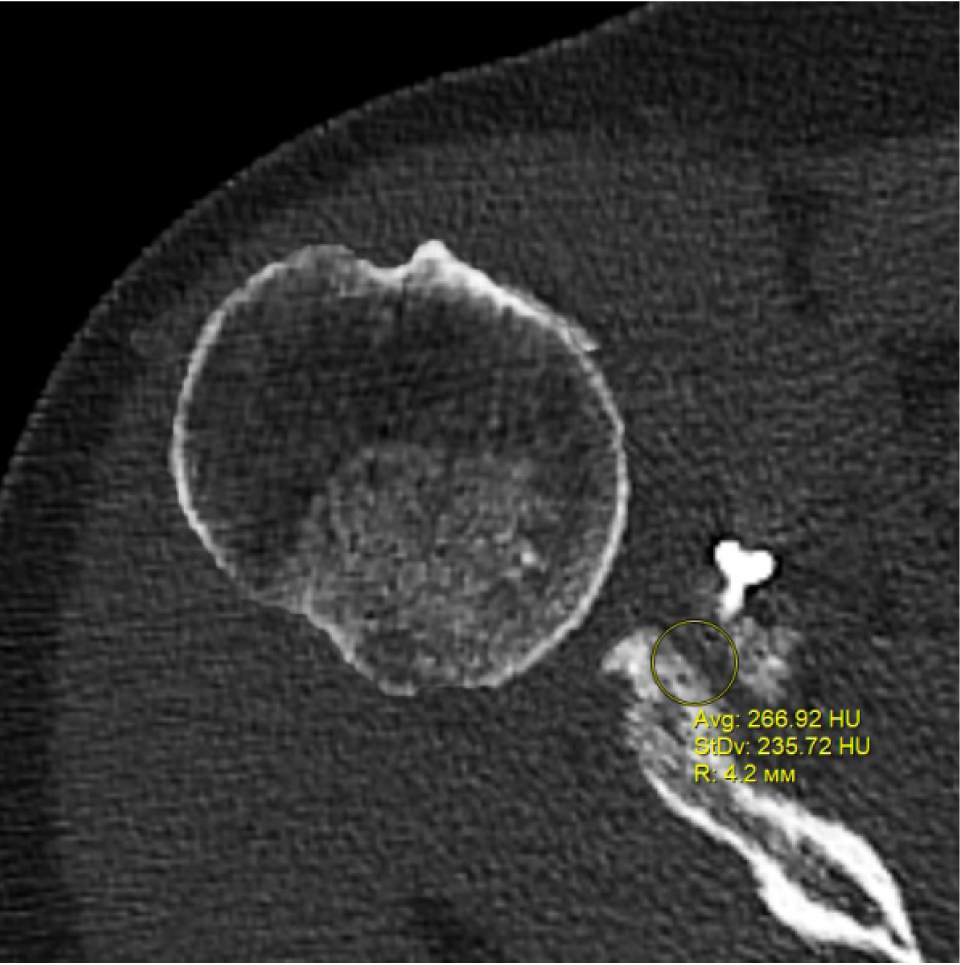

В программном обеспечении, на аксиальных КТ срезах оперированного плечевого сустава, выбирали инструмент «круг», который позволял посчитать среднюю плотность тканей внутри круга в единицах Хаунсфильда. Шкала единиц Хаунс-филда (HU) – шкалалинейного ослабления излучения по отношению к дистиллированной воде, рентгеновская плотность которой была принята за 0 HU (при стандартных давлении и температуре). Круг устанавливали таким образом, чтобы одна его половина была заполнена тканью гленоида, вторая половина тканью трансплантата (рис. 1–3). Оценивали плотность тканей над проксимальным винтом, между винтами, под дистальным винтом. Полученные данные анализировали с помощью пакета Microsoft Excel.

Рис. 1. Оценка плотности ткани под дистальным винтом

Через 3 месяца после оперативного лечения по данным анализа КТ срезов были получены следующие результаты: плотность ткани над проксимальным винтом составили (424 ± 24,3) HU, между винтами (460 ± 23,4) HU, под дистальным винтом (587 ± 49,1) HU. Спустя 6 месяцев после операции плотность ткани над проксимальным винтом составили (320 ± 28,7) HU, между винтами (424 ± 36,2) HU, под дистальным винтом (623 ± 33,4) HU. Через 12 месяцев после операции показатели были следующие над проксимальным винтом (276 ± 22,1) HU, между винтами (387 ± 31,1) HU, под дистальным винтом (662 ± 43,2) HU (таблица).

Над проксимальным винтом | 424,0 ± 24,3 | 320,0 ± 28,7 | 276,0 ± 22,1 |

Под дистальным винтом | 587,0 ± 49,1 | 623,0 ± 33,4 | 662,0 ± 43,2 |